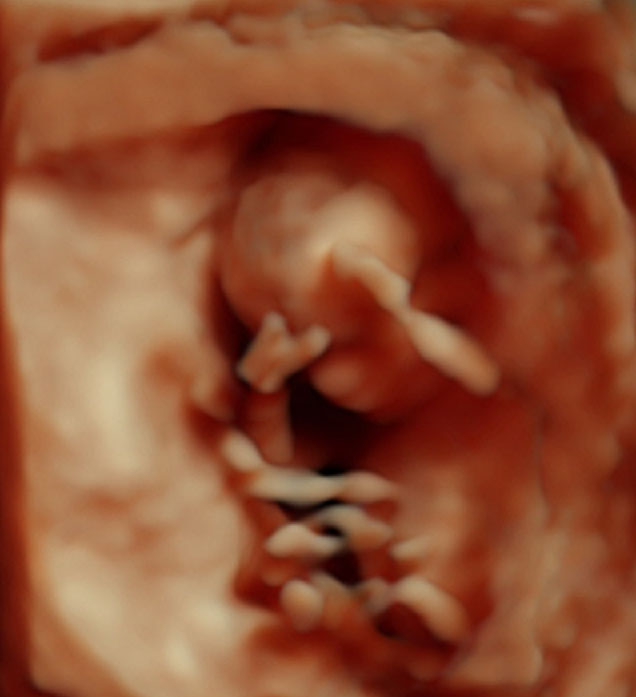

Vis vedlegget 58299Her er nurket vårt :) 95 prosent sjans på at det blir ei jente!!!!! Lykke!!!! Alt var super bra :) Vokste som hun skulle :) Og han legen sa terminen var 25. oktober :) Men samme det! Lykke :D

Såååå liten å Skjønn <3 så bra kvalitet på bilde da